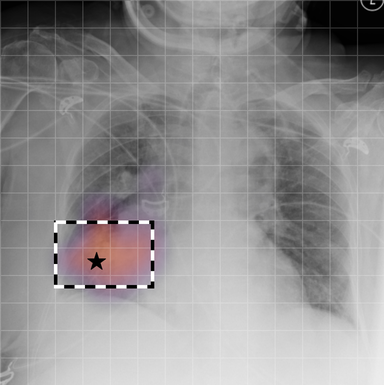

| (1) |

for , where denotes 2D sinusoidal positional encodings [12] and is its temporal counterpart, which is learnt (Fig. 2) [4]. The layer-normalised () [6] output of the final transformer encoder block is an ‘aggregated’ representation of patch-level progression information anchored on the current image. Figure 3 shows attention roll-out [1] applied to after pre-training, showing how the prior image contributes to the fused representation. Figure A.5 further highlights the robustness to variations in pose underlining that registration is not necessary for this encoder.

In Figure A.3, we show examples of self-attention rollout [1] maps for pleural effusion and consolidation, including radiologist-annotated bounding boxes surrounding the corresponding pathology in each prior and current image.

To model the attention flow through the transformer encoder block, we first average each attention weight matrix across all heads, subsequently we multiply the matrices between every two layers. For every block we add the identity matrix in order to model the residual connections. Last, we only keep the top 10 of attention weights per block to reduce noise in the final rollout map. In contrast to [21], we do not visualize the rollout map with respect to a [CLS] token. Instead, we choose a reference image patch from the center of the radiologist-annotated bounding boxes, marked with in Figure A.3.

We find that the rollout maps in Figure A.3 are in good agreement with radiologist-annotated bounding boxes, i.e., the reference patch attends to other patches within the bounding boxes in the prior and current image. In addition, we find that BioViL-T is robust to pose variations, e.g., in Figure A.3 (a) we show that despite the vertical shift between prior and current image, the reference patch attends to the correct image patches in the prior image.